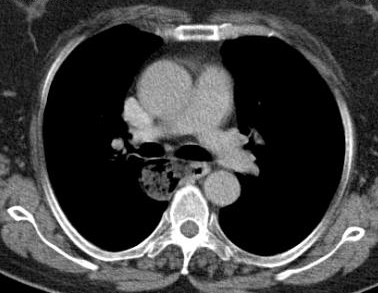

Esophageal diverticula are acquired conditions almost always occurring in adults where the epithelium-lined blind pouch arises from the esophagus. They are categorized primarily by anatomic location and etiology into pulsion and traction diverticula. Zenker and epiphrenic diverticula are false diverticula, while midthoracic diverticula are usually traction diverticula that occur secondary to mediastinal inflammation and fibrosis in adjacent lymph nodes and are true diverticula [1, 2]. Traction type is more common in developing countries [3]. Most esophageal diverticula are found incidentally. The diagnosis is usually made on barium swallow (Figures 1a, 1b). Esophageal endoscopy by an experienced endoscopist is recommended to exclude other etiologies for dysphagia. Chest CT is helpful in the differential diagnosis and identifying the extent of the diverticula (Figure 2). Esophageal manometry typically shows motility disorder, however it is very difficult to advance the pressure probe through the esophagus. Indications for surgery are large sized (>4-5 cm), moderate to severe esophageal symptoms and complicated diverticula [3, 4]. Our patient selection for VATS approach was large midthoracic diverticula and severe esophageal symptoms.

- Figure 2. CT scan of a patient with midthoracic diverticulum. The diverticulum fails to drain properly and has food particles in it.